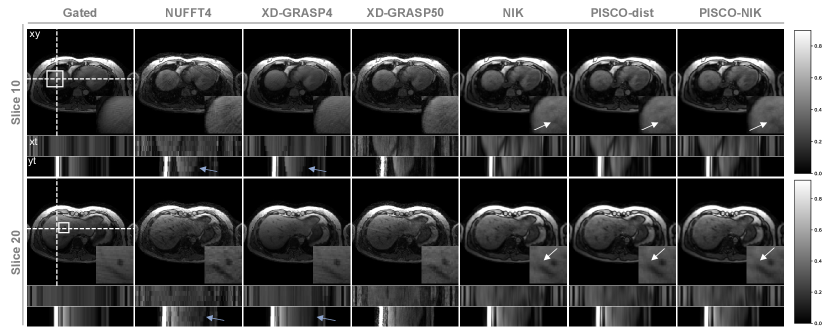

Abdominal

Fig. 7 shows reconstructions of exemplary slices of the abdominal data. The reference unpaired prospectively GATED acquisition, common in a clinical setting, shows a spatial smooth image, but still appears slightly blurry at the organ edges and lacks temporal information overall. Motion-resolved reconstructions with 4MS retain undersampling artefacts (INUFFT4) or lose temporal information (XD-GRASP4). Increasing the temporal resolution by binning to 50 MS (XD-GRASP50) improves the dynamic depiction, but suffers from noise and undersampling. NIK, PISCO-dist and PISCO achieve high spatiotemporal resolution, with PISCO further smoothing results both spatially and temporally.